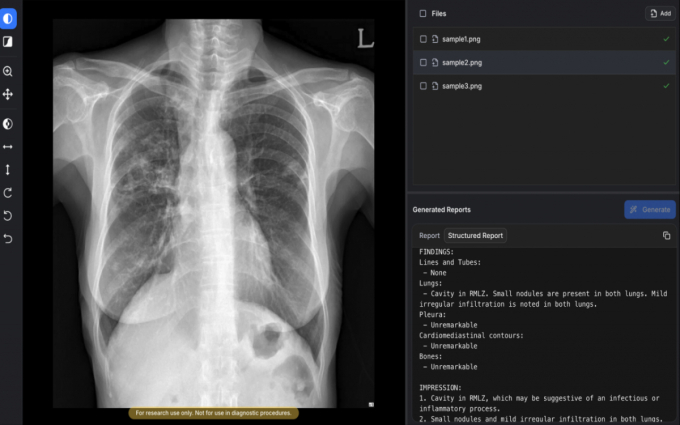

의료 AI(인공지능) 기업 숨빗AI가 식품의약품안전처로부터 흉부X선 예비소견서 생성 솔루션 '에어리드-씨엑스알'(AIRead-CXR)에 대한 3등급 인허가를 획득했다고 2일 밝혔다.

AIRead-CXR은 국내외에서 확보한 약 1400만건의 데이터를 학습해 다양한 병원 환경에서 촬영된 PA(뒤에서 앞으로 찍는 방식) 또는 AP(앞에서 뒤로 찍는 방식) 흉부X선에 대해 안정적으로 예비소견서를 제공한다.

검증된 57개 소견 및 질환에 대해 높은 수준의 판독보조 성능을 제공할 뿐 아니라 이외의 다양한 영상 소견도 해석·언급할 수 있다. 임상 현장의 실제 워크플로우를 반영해 의료진이 보다 효율적으로 판독 업무를 수행할 수 있도록 설계됐다.

공개된 임상논문에 따르면 흉부영상 전문의들이 평가한 AI 예비소견서 평균 수용도는 85%로, 비교 대상인 구글 딥마인드의 AI 모델 'MedGemma'(66.9%)를 상회했다. 환각(할루시네이션) 비율은 0.3%로, MedGemma(9.7%) 대비 우수한 안정성을 보였다.